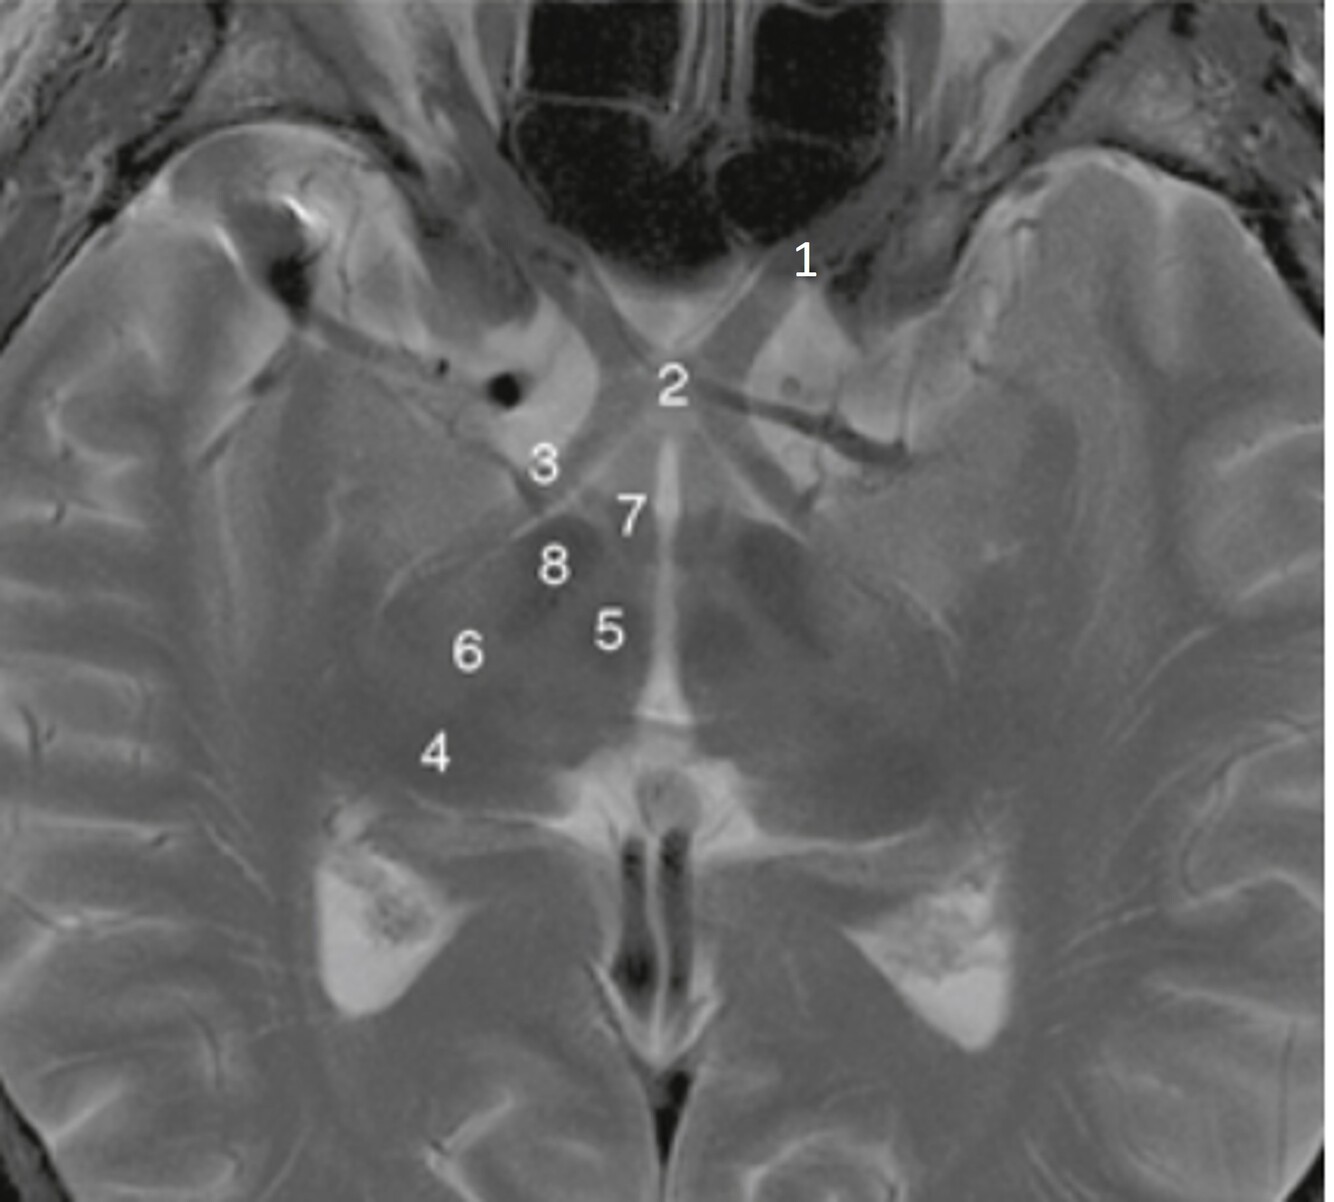

23

Label a,b,c,d,f,g

A

a-Rt lateral fissure

b=Insula

c=Quadrigeminal cistern

d-3rd ventricle

f-Cerebellum

g=Anterior horn (of rt lateral ventricle)